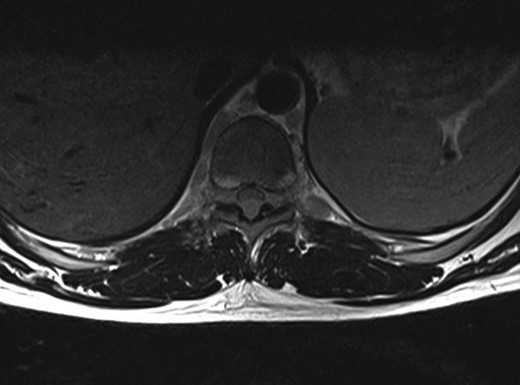

A 30-year-old male patient was admitted to our clinic with back pain. Pain was provoked by movements. The severity of pain was associated with the inability to perform the activities of daily living. The patient did not have any lymphoma-related B-type symptoms, including body weight loss, fever and sweat at night. He did not have a past and family history. There was no neurological deficit. Routine laboratory test results were normal. A magnetic resonance imaging (MRI) scan of the thoracic spine demonstrated an epidural tumor at the T9–11 level (Figs 1–3). The patient underwent spinal cord decompression via total laminectomy of T9–11 levels. Subtotal resection of the tumor was performed. Histological examination revealed the polymorphous cellular infiltration by histiocytes, large mononuclear cells and lacunar Reed–Sternberg cells with folded multi-lobed nuclei and small nucleoli (Fig. 4). Immunohistochemical staining was positive for CD15 and CD30 and negative for CD3, CD20, CD79a or CD45Ro. These features were most frequently observed in the mixed cellularity type of Hodgkin's lymphoma. Histological examination of the vertrebral body revealed no abnormality. The results of all other examinations (F-18 fluorodeoxyglucose positron emission tomography (F-18 FDG PET/CT), bone marrow biopsy and computed tomography (CT) of the chest, abdomen and pelvis) were negative for an occult disease. The patient was referred to the hematology department to undergo staged treatment. Six courses of chemotheraphy containing ABVD regimen (adriamycin, bleomycin, vinblastine and dacarbazine) were given to the patient. Postoperative MRI scan did not reveal any evidence of Hodgkin's disease (Fig. 5), F-18 FDG PET/CT, CT of the chest, abdomen and pelvis were obtained in 24 months and did not reveal any evidence of Hodgkin's disease.

Moridaira et al. [4] reported a case of Hodgkin's disease at T8–10 epidural space. Rao et al. [6] published a case with primary spinal epidural Hodgkin's lymphoma. Our case is apparently the seventh case to be diagnosed with Hodgkin's disease who presented with spinal cord compression due to epidural space without lymphoma elsewhere. The abnormal MRI marrow signal of the T9 and T10 vertebral bodies can be seen in Fig. 5. Maybe the tumor in fact originated within the abnormal T9 or T10 bone marrow and spread to the epidural space via the epidural venous plexus. But histological examination of the vertebral body revealed no abnormality.

Surgery is the first therapeutic approach in malignancies compressing the spinal cord. Because Hodgkin's lymphoma is a very chemosensitive and radiosensitive tumor, the indications for surgery were reduced and limited to laminectomy or even biopsy only, leaving the major role to chemotheraphy and radiotheraphy. The combination of chemotheraphy and involved-field radiotheraphy is the most common treatment strategy; two to four cycles of ABVD are considered as the international gold standard for early-stage Hodgkin's lymphoma in combination with 20–30 Gy of involved-field radiotheraphy [7, 8]. We chose the first therapeutic approach for this patient who underwent gross total resection of the tumor, because the tumor type was unknown at the time of initial presentation. Also, there was severe thoracal spinal cord compression on MRI of our case. Then, the patient was given six courses of chemotheraphy through ABVD regimen.